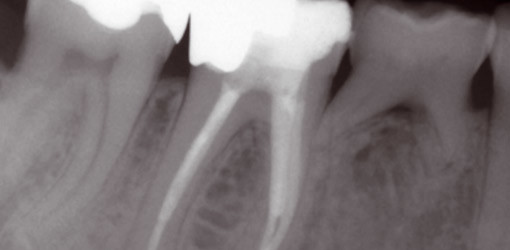

Häufig findet man in der Einleitung neuerer Artikel die Bemerkung, dass sich die Endodontie innerhalb des letzten Jahrzehnts dramatisch verändert...

Die technischen Verbesserungen erlauben heute die sichere vorhersagbare Therapie komplexer anatomischer Situationen. Dennoch führen manche Therapien...

Zur Wurzelkanalaufbereitung haben sich verschiedenen Techniken bewährt. Prof. Dr. Rudolf Beer stellt im folgenden Artikel die Step-back-Technik,...